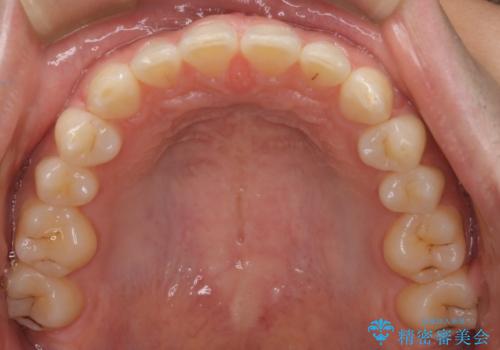

再矯正ということでがたつきはなくきれいに並んでいましたが、上下のアーチ(歯列弓)の大きさのバランスが悪く、結果的に後戻りの原因になってしまっていました。今回は下のアーチを小さくするためにIPRを行い、かみ合わせのバランスを治しながら前歯の隙間を閉じました。